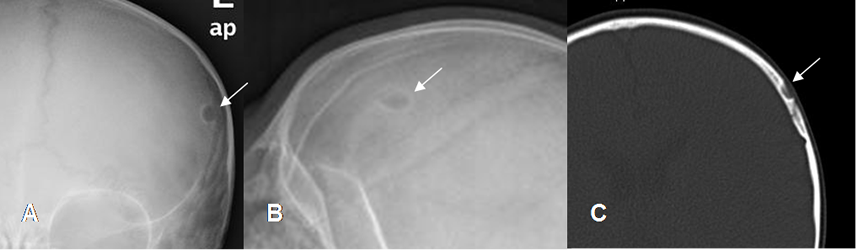

Fig 132. Granuloma eosinófilo.

A: RM axial en T1, B: RM axial en T2 y C: RM axial en T1 con contraste. Lesión frontal izquierda hipointensa en T1, hiperintensa en T2 y que realza con el contraste, por granuloma eosinófilo.